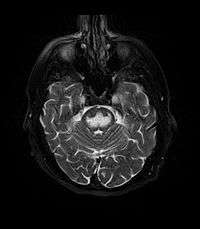

It can be difficult to identify using conventional imaging techniques. It presents more prominently on MRI than on CT, often taking several weeks after acute onset of symptoms before it becomes identifiable. Imaging by MRI demonstrates an area of high signal return on T2 weighted images.